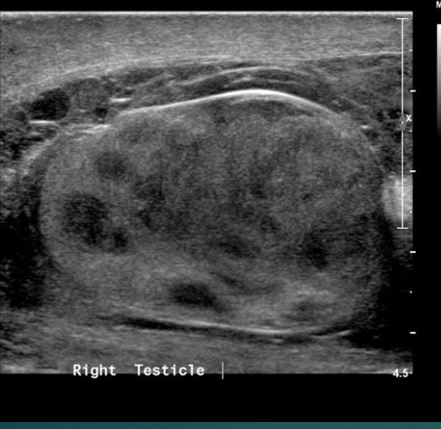

what does this image show

Varicocele

what does the image show

torsion